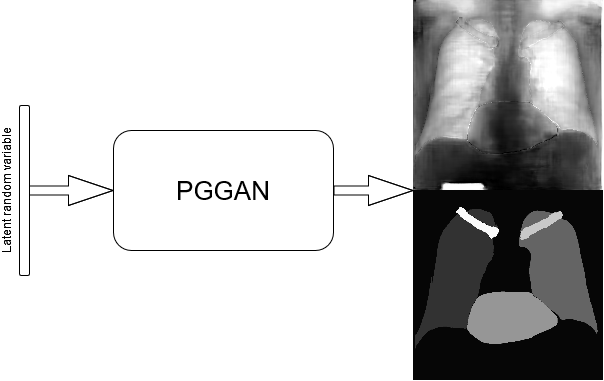

This baseline approach consists in stacking X–ray images and labels into two different channels, which are simultaneously fed into the PGGAN. Therefore, the PGGAN is trained to generate pairs composed by an X–ray image and its corresponding label (see Figure 1).